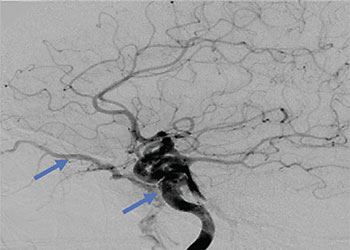

Endovascular:

CME:

Direct Carotid Cavernous Fistula (CCF)

Author: Jonathan L. Brisman M.D., F.A.C.S., Read More!